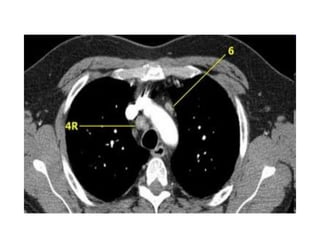

Haïch caïnh khí quaûn döôùi -4R.

4. HAÏCH CAÏNH KHÍ QUAÛN DÖÔÙI

Naèm döôùi ñöôøng ngang veõ tieáp tuyeán bôø treân

cung ñoäng maïch chuû.

4R-Haïch naèm beân (P) ñöôøng giöõa khí quaûn.

4L-Haïch naèm beân (T) ñöôøng giöõa khí quaûn môû roäng ñeán pheá quaûn